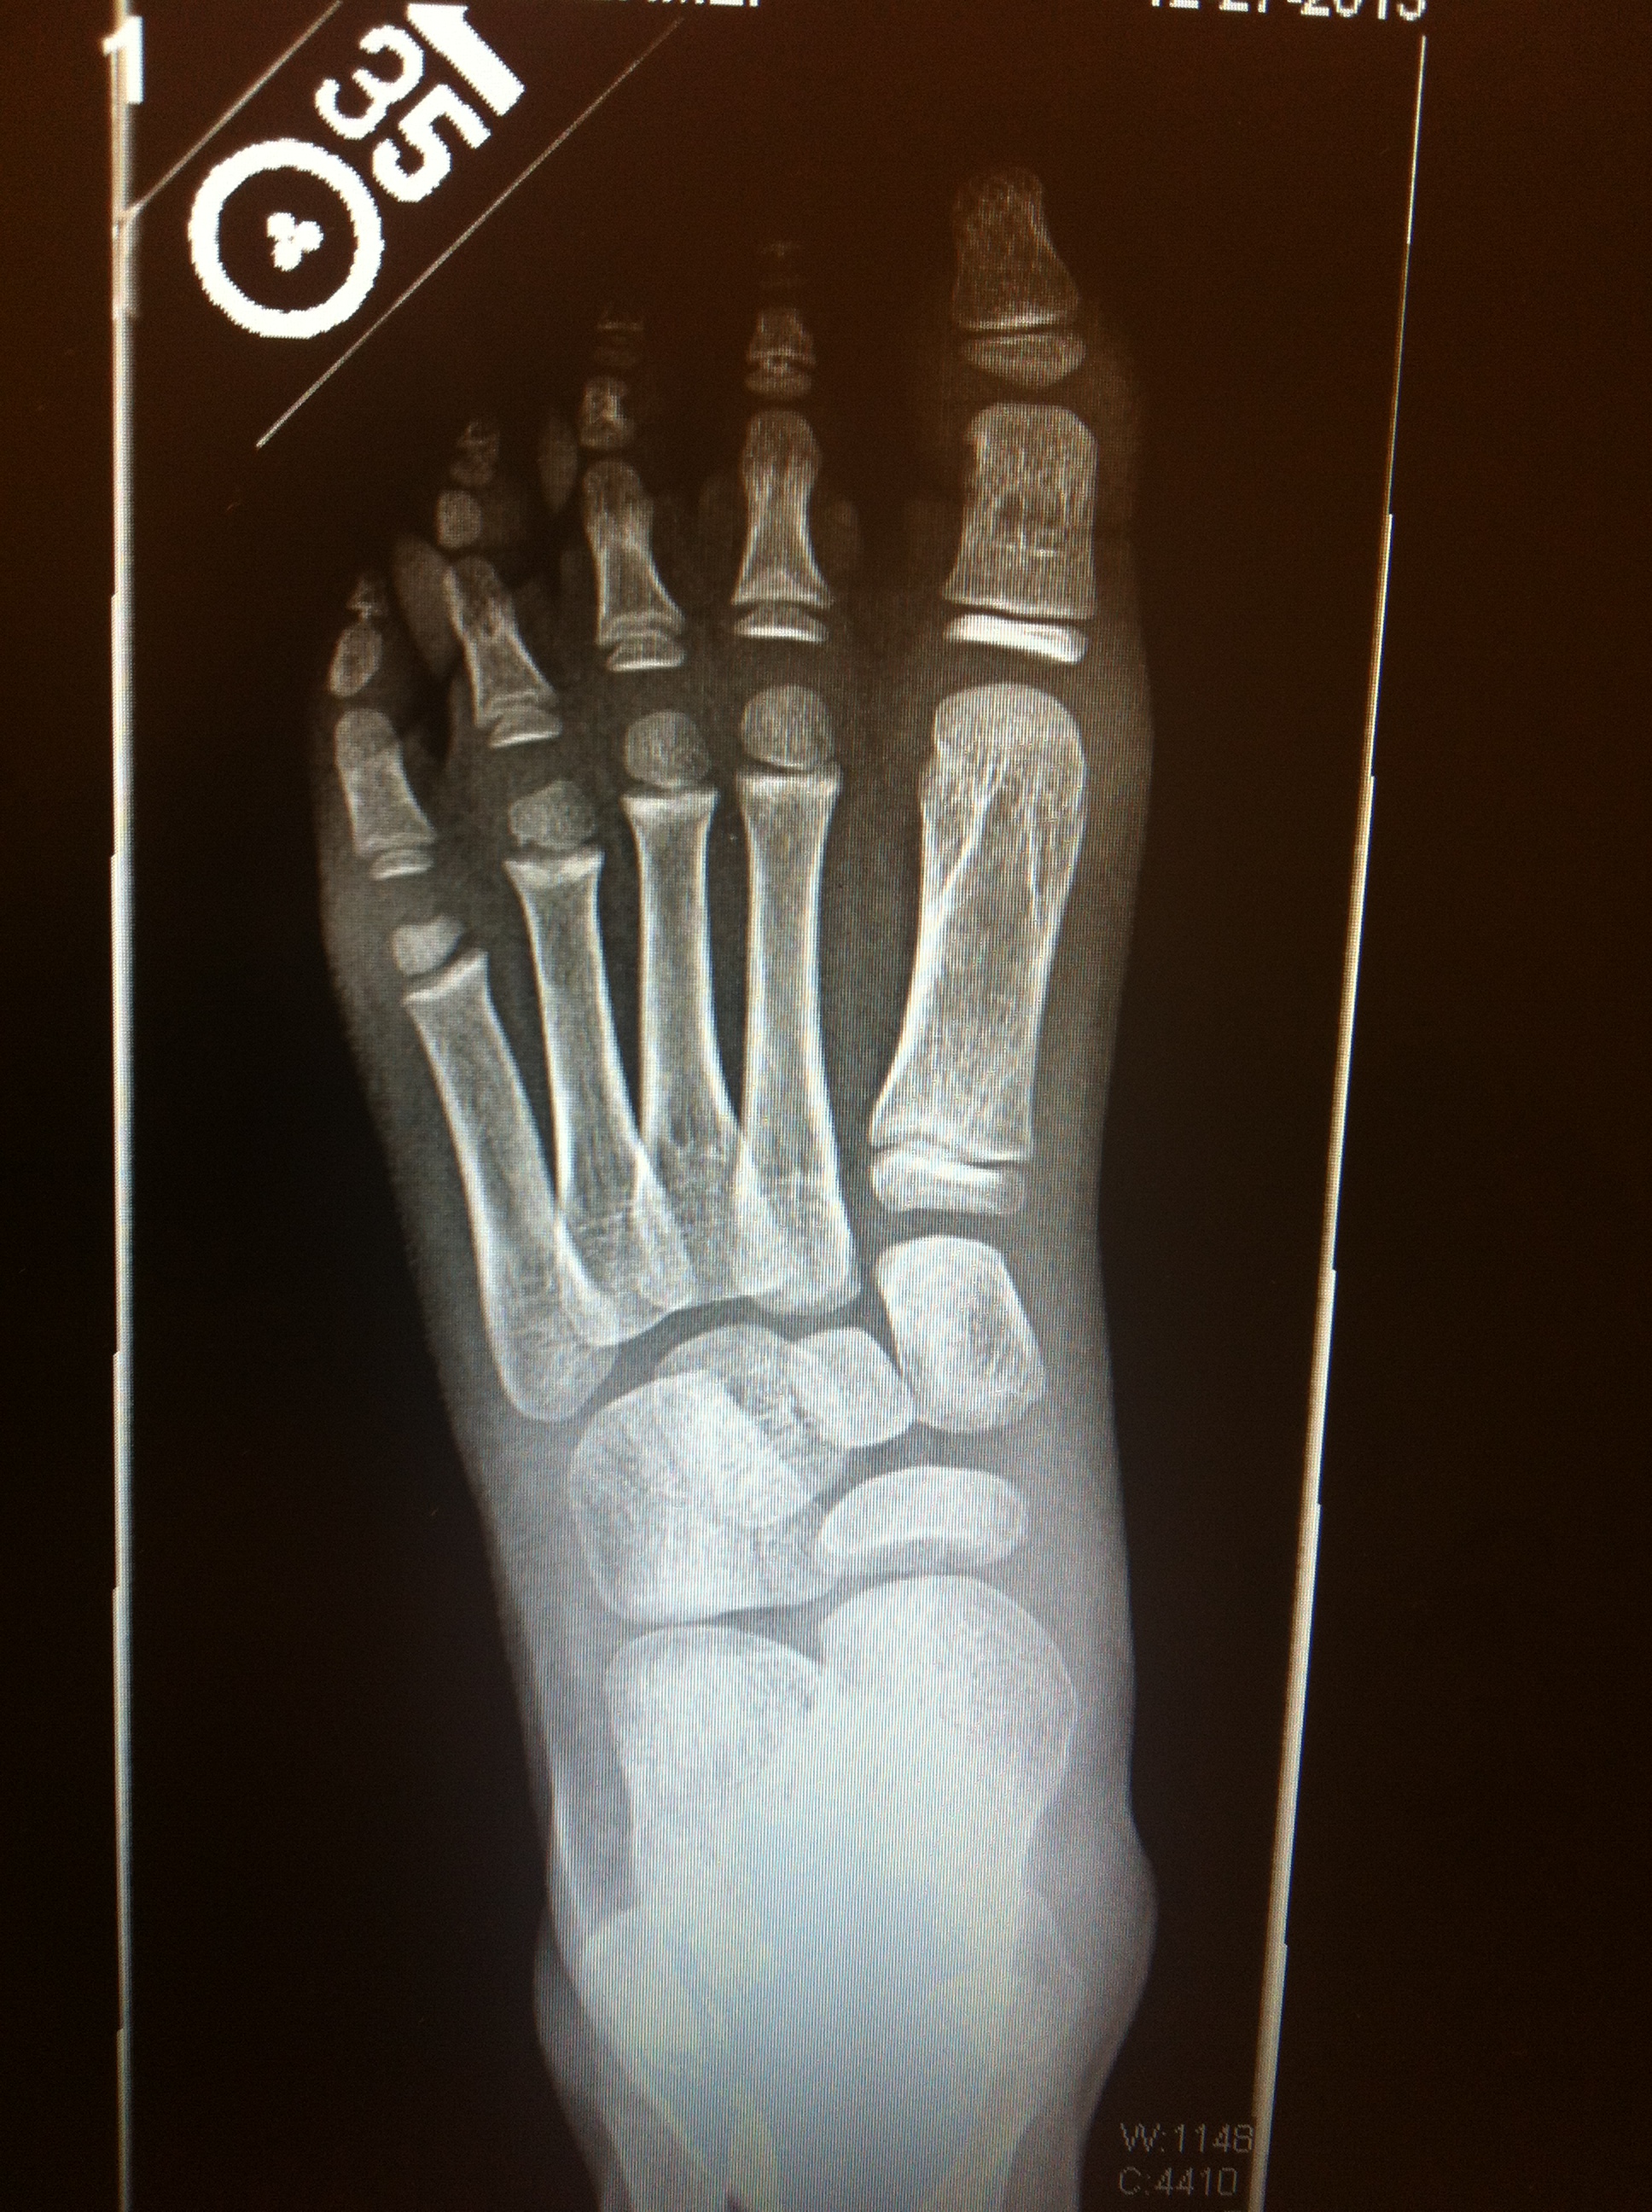

We iced her foot and went to the pediatric orthopedic clinic that we visited just a short six months ago. There she got her three view X-rays: AP, oblique, lateral. The words, “THERE IS NO OBVIOUS FRACTURE” that came out of the orthopod’s mouth was the best Christmas present this year. We had the choice of a hard cast or a moon boot. We chose the moon boot so that we don’t have to deal with the hassle of having to keep the hard cast dry all the time like we did with her arm.